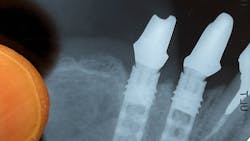

- Radiograph: I always request x-ray images downloaded from the software. (I’d rather not get a picture taken of image on the computer screen.) This allows me to play with the balance, contrast, brightness, and size of the picture, which makes identification so much easier. I have every implant catalog I have ever received from every sales rep in the last four decades for reference.

- Implant interface: Look at the interface rather than the implant body. I can look at any x-ray and expand the interface of the implant and look for internal or external hex. If, for example, it looks like a Brånemark regular-diameter implant, I’m done. If the diameter is wider or smaller, I’ll check the platform versus the hex to further establish which implant company made this diameter of implant. For example, Nobel Biocare had wider- and smaller-diameter implants where the external hex and thread hole are wider to match. 3i had wide and narrow implant platforms with the same external hex and thread hole as the regular diameter. This makes a Nobel Biocare 5 mm implant incompatible with the 3i 5 mm. In the case of the Core-vent Zimmer implant, it’s very easy. The regular has a taper, and the wide implant is flat. The internal hex connection is the same for both sizes. If the implant is an original Core-vent, there will be a hole at the bottom of it. Straumann Tissue Level is the easiest to identify, but some clones have changed the thread and internal connection. In this case, we cannot use Straumann parts but instead need to get the parts designed by the manufacturer of the implant. Unfortunately, many of these companies have long gone out of business.